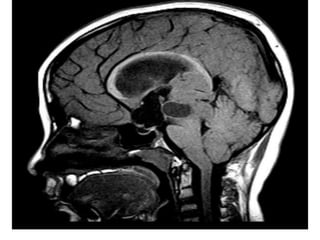

T1+C shows a slightly hypointense tectal mass which does not

enhance , the mass obstructs the aqueduct and is stable over

8 years

*T1+C :

-Usually no enhancement

-Higher grade tumors tend to be larger and tend to

enhance more vividly